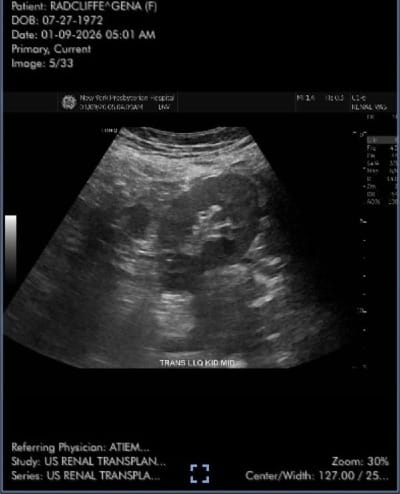

The "amazing opportunity" was that the kidney was from a living donor, whereas I had been expecting to get one from a deceased donor. Unbeknownst to me, my transplant center participates in a program that matches kidneys from failed paired donations to patients on the deceased donor list. A living donor kidney is a game changer: the kidney "wakes up" faster, there are generally less complications post-surgery, and the projected life of the kidney itself at least doubles. While dumbfounded and not quite sure I hadn't dozed off the train and was dreaming, I accepted, quickly went home to gather my go bag, and went up to New Presbyterian-Weill Cornell Hospital in Manhattan. Less than four hours after I got there, I was on the table, and, well, I have a new kidney.

I was out of the hospital by Monday, which was not, as a lot of people have assumed, an insurance-based decision. 4 to 6 days in hospital is the general timeframe for most kidney transplants these days, barring any complications, because modern science is its own miracle, and once they have your pain managed and you're walking, eating, and pissing on your own there's not much more they can do you for than you can do for yourself at home. Other than I fucking hated and whined constantly about how uncomfortable the catheter was (negative stars), I did fine. My kidney started waking up right away. I managed to take a mile's worth of steps around the ward by my third day, the same day I started eating solid foods. The pain wasn't too bad, mostly manageable with Tylenol. And oh boy, am I peeing. I am peeing SO MUCH, you guys.